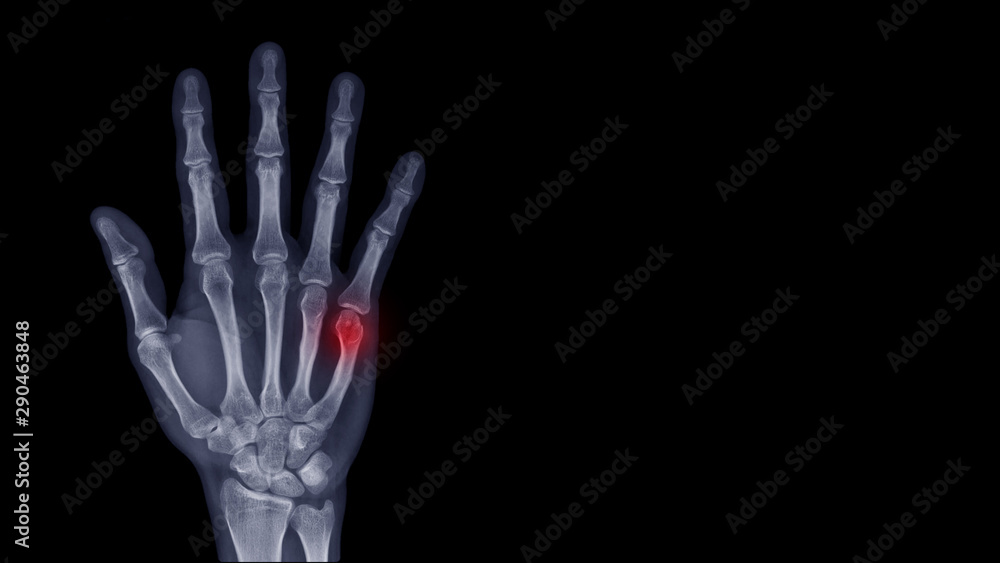

From stock.adobe.com

Film Xray hand radiograph show finger bone broken (fifth metacarpal Metacarpal Fracture Return To Sport  The purpose of this study was to. Metacarpal fractures are common in football players and lead to time away from competition, but current operative treatment data is limited. A variety of operative and nonoperative treatment strategies have been proposed to achieve anatomic restoration, fracture stability, and. Metacarpal Fracture Return To Sport.